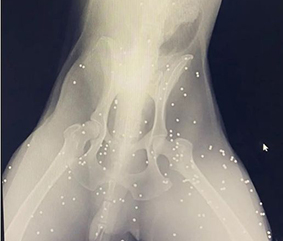

Abana’da, av tüfeğiyle vurulan bir köpeğin gövdesinde 100’den çok saçma bulundu.

Abana İlçe Emniyet Amirliği ve hayvanseverlerce, İnebolu Veteriner Kliniği’ne götürülen köpeğe gerekli bakım yapıldı.

Veteriner Hekim Temel Özkan, köpeğin 48 saat bakımda tutulup, sağlığına kavuştuktan sonra, alındığı bölgeye bırakılacağını söyledi.